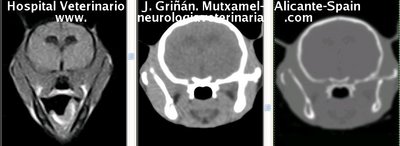

Se muestran cortes transversales de Resonancia Magnética (imagen a la izqda del lector), TC contrastado para tejidos blandos (imagen del centro) y TC contrastado para tejidos duros (imagen de la derecha del lector).

Nótese como la Resonancia supera al TC en el contraste de tejidos blandos (encéfalo y médula espinal) y en el de líquidos (ojo y líquido cefalorraquídeo), mientras que el TC supera a la resonancia en el contraste de tejidos duros (hueso) y aire (senos, cavidad nasal y bullas)

Cortes a nivel de los lóbulos cerebrales frontales